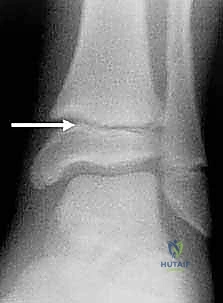

If there is no radiographic demonstration of displacement, the iliac wings can be compressed to test for stability of the pelvic ring and each hemipelvis. A careful examination of the skin to identify areas of ecchymosis and hematoma formation, particularly in the flanks, groin, and abdominal regions, also needs to be performed. The presence of a Morel-Lavallée lesion indicates that high-energy trauma has occurred in the pelvic region ( FIG 4). Recognition of this lesion is important to prevent infection and may need to surgically decompressed, prior to proceeding with definitive fixation of the symphysis.

FIG 4 • Morel-Lavallée lesion. A good pelvic examination and evaluation of the perineum are essential. Swelling or open wounds in the perineal area may indicate a high-energy mechanism of injury. Open injuries require emergent management. Evaluation of other organ systems, looking for associated injuries, is essential. In males, a high-riding prostate on the rectal examination or blood at the meatus may indicate injury to the urethra or bladder, and placement of a Foley catheter should be delayed until a retrograde urethrogram is performed, unless the patient is in extremis. Urethral injuries are less common in females because the urethra is shorter. A thorough neurologic examination of the lower extremities also needs to be performed as injuries to the L4 and L5 nerve roots can occur in pelvic fractures. It is essential to test the sensation and motor functions of specific roots, identifying any neurologic injury that can differentiate between a nerve root lesion or a more central lesion. A limb length discrepancy or a rotational deformity of the lower extremities should prompt radiographic evaluation of the pelvis. ## IMAGING AND OTHER DIAGNOSTIC STUDIES Radiographic evaluation of the pelvis consists of anteroposterior (AP), inlet, outlet, and Judet views ( FIG 5). A retrograde urethrogram and sometimes a computed tomography (CT) cystogram should be performed to rule out an injury to the genitourinary system in men. A CT cystogram is sufficient for females. A CT scan of the pelvis is also indicated to help evaluate intra-articular injuries to the sacroiliac joints and further delineate the fracture pattern. A CT angiogram can also be used at the time of the trauma scan to help predict if an arterial bleed is present and requires further treatment with angiography and embolization. 10 Angiography may be used to treat patients who are hemodynamically unstable and do not respond to standard resuscitation, particularly if a CT angiogram indicates arterial bleeding. A stress examination in the operating room can be performed under fluoroscopy to assess stability if there is a question of an unstable pelvis. Single-leg stance (also known as